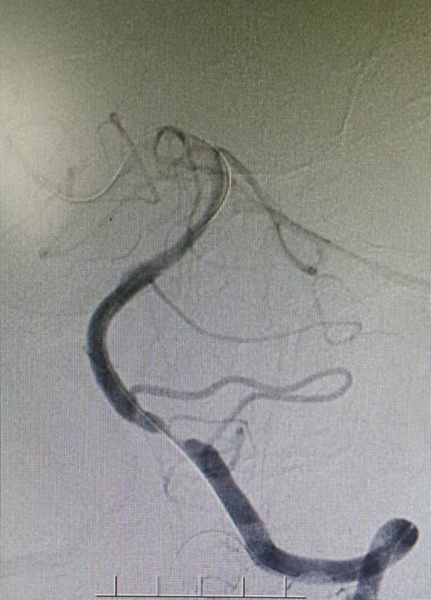

入院影像检查

导丝怎么扩【载药时代 球扩天下】NOVA DES®颅内药物洗脱支架在症状性颅内动脉狭窄中的应用—烟台鲁东医院使用体会二例!_https://www.jmylbn.com_新闻资讯_第19张

重要影像结论:右侧颈内动脉C6段重度狭榨。

重要影像结论:右侧颈内动脉C6重度狭窄(90%)。

诊断

主要诊断:右侧颈内动脉C6段重度度狭窄

病变部位:右侧颈内动脉C6段

远端正常血管直径(mm):3.1

狭窄处最小直径(mm):0.5

病变长度(mm):10

狭窄度(%):90%以上